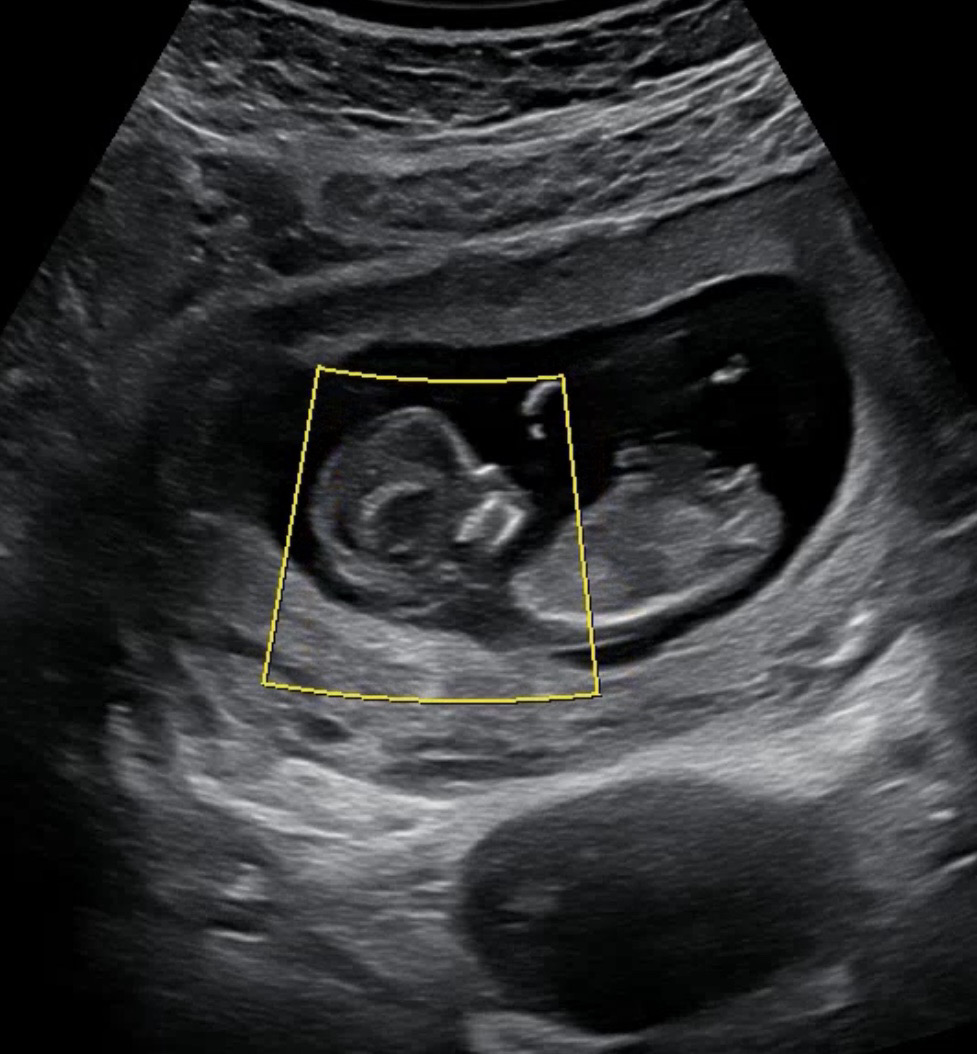

제 눈엔 딸같은데 어떤가요?

ㅎㅎ아가 자세 기울기가 좀 있어요 ! 제 눈엔 딸같은데 어떻게 생각하세요?

저도 자세땜에 줄그어보니 좀 보기쉽더라구요ㅎㅎ 잘못보지만 좀솟은고같기두해요.. ❗️

앗 ㅎㅎㅎ 댓글감사해요! 척추끝에서 일직선 그어보니까 아들이라기엔 좀 완만해서! 끝도 갈라져있구 그래서 딸이라고 생각한거같아요 :) 가랑이두 안보여가지구 ㅎㅎㅎ